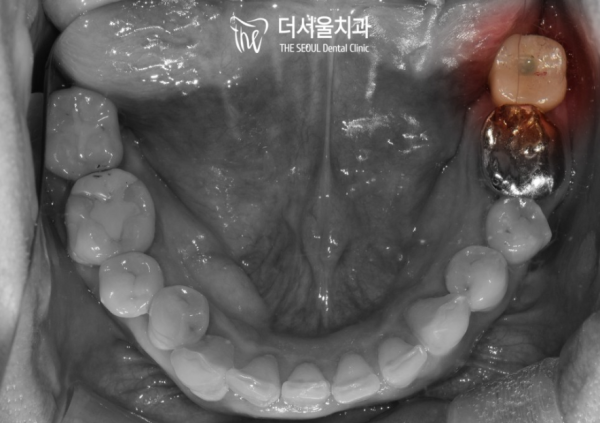

육안으로 관찰하여도 누워있는 사랑니가 보입니다.

이런 형태로 자라는 사랑니는 대부분의 경우 인접한 치아에

안좋은 영향을 끼치게됩니다.

실제로 사랑니와 어금니 발치 후 임플란트를 식립한 모습입니다.

깔끔하고 튼튼하게 임플란트가 심어진 모습을 확인할 수 있습니다.

이 환자분의 케이스는 사랑니를 제때 검진하고 발치 하지 않아

바로 인접한 어금니까지 발치를 하게된 사례입니다.

이렇게 누워있는 사랑니는 거의 무조건 발치를 하는것이 좋은 경우가 많습니다.